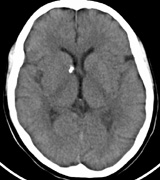

INTRACRANIAL LESIONS.

Mental retardation and seizures in TSC are often associated with benign CNS astrocytic hamartomas.131 On imaging, the cerebral lesions show three patterns:132

1. Superficial cortical sclerosis (parenchymal hamartoma) which distort the gyri. Microscopy shows large atypical fibrillary type astrocytes with few associated neurons and areas of calcification.133 The numerous abnormal glial processes and fibers make the tissue abnormally firm or “sclerotic” on palpation (Fig. 13).132

2. Subependymal nodules (SEN) are typically found along the lateral borders of the ventricles and parehncymal brain lesion (“cortical tubers”) (Figs. 14 and 15). Calcification in the first year of life is rare.132

3. White matter abnormalities are a characteristic “ventriculofugal” pattern corresponding to the embryological migratory paths of neurons and glia. These lesions may represent aberrant neuronal migration, a possible reflection of haploinsufficiency for the TSC gene.116,132,134

On MRI imaging, the subependymal nodules and parenchymal brain lesions of infants (age ≤3 months) and adults show different signal characteristics. Infant CNS tubers are hyperintense on T1-weighted images and hypointense on T2-weighted images, which is the opposite of the pattern seen in adults.134 Malignant transformation of SEN occurs in about 10% to 15% of patients and the resultant subependymal giant cell astrocytoma accounts for 25% of premature deaths in TSC.135,136

Fig. 14. Tuberous Sclerosis Complex: Sub-Ependymal nodules. These are typically found along the lateral borders of the ventricles.132

Fig. 15. Tuberous Sclerosis Complex. (a) Patient 1: Axial CT scans demonstrating typical calcification of subependymal nodules in a 13-year-old girl with a history of seizures. (b and c) Patient 2. (b) Axial T2-weighted images demonstrate calcified subependymal nodules (arrowheads) and cortical tubers typical of tuberous sclerosis. (c) Widespread cortical tubers are seen on a coronal FLAIR sequence as thickening of the cortex and high signal of the subcortical white matter.